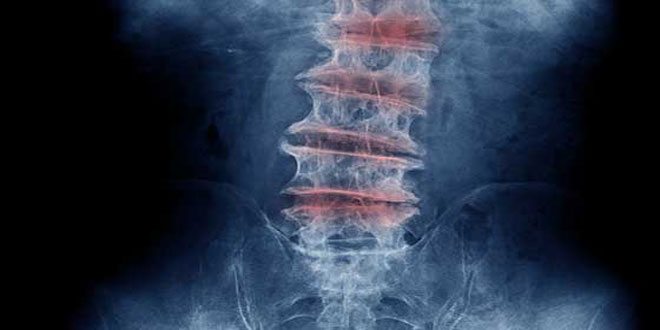

توصل باحثون من جامعة “سيدني كيميل” الطبية الأمريكية إلى مزيج من الأدوية يقلل من حدوث مرض تنكس الأقراص الفقرية لدى الإنسان.

ويعتبر مرض تنكس الأقراص الفقرية من المشاكل التي تحدث في الأقراص المبطنة للفقرات والمدعمة لها وهو مرض شائع في الشيخوخة ويعد أحد العوامل الرئيسية المساهمة في آلام أسفل الظهر.